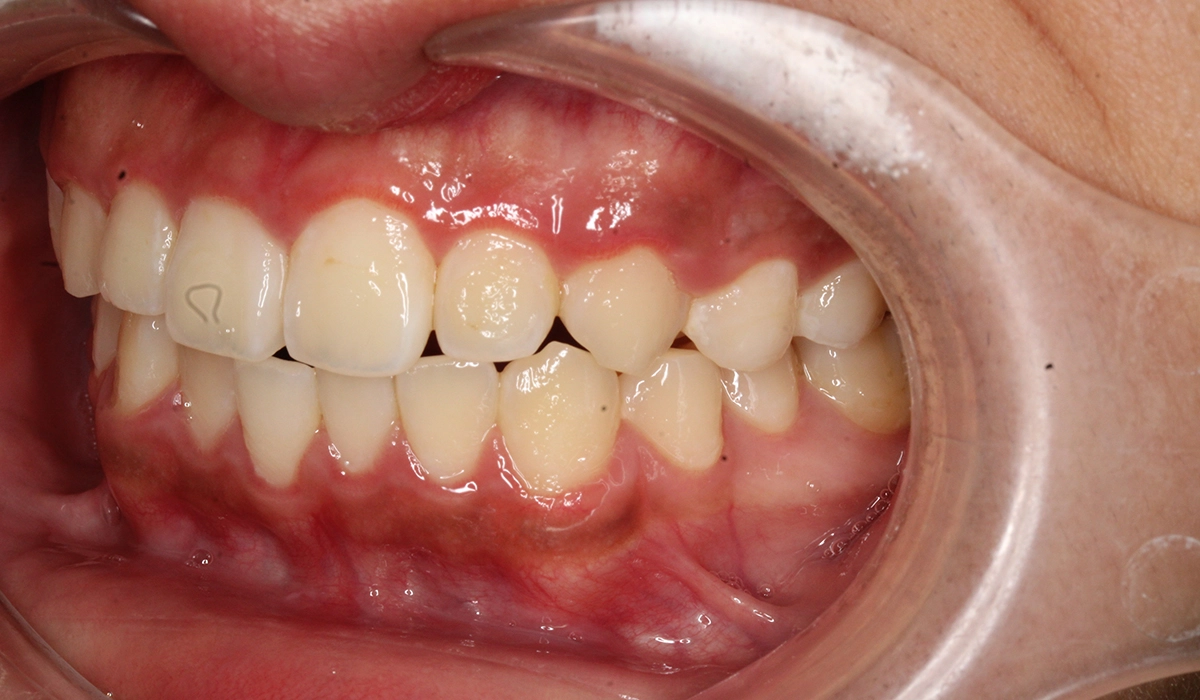

術前:右側